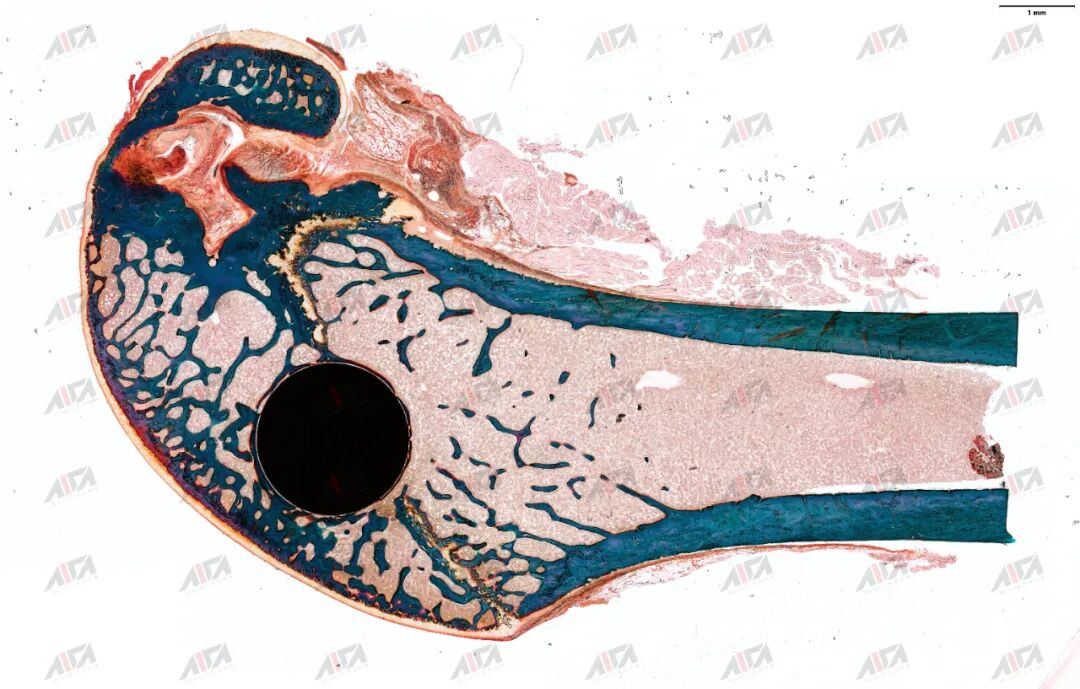

图片

硬组织切磨片-HE染色

硬组织切磨片-Masson-goldner染色